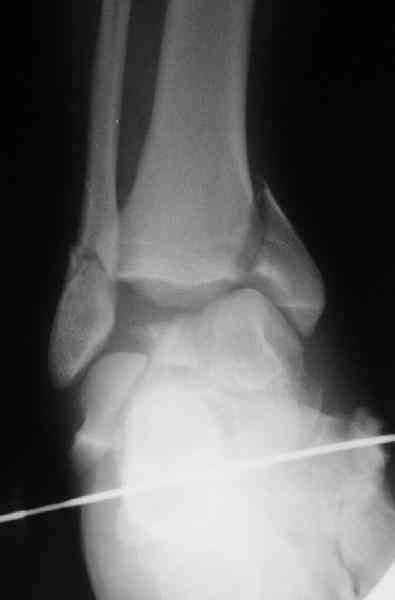

И второй случай из недавней ташкентской практики, (извините за качество ренгенограммы и только в одной проекции) случай падения с высоты (кстати моего друга - известного киноактера) - открытый

смещенный перелом тарана, с переломом переднего края дистального эпиметафиза большеберцовой кости.

При поступлении в приемной сделана первичная обработка с ушиванием открытой латеральной раны и вытяжением за пятку.

Из-за отсутствия времени пришлось оперировать на второе утро, из материала, что имеем на месте, фиксирован двумя шурупами, а третий-это контур сломанного жойстика в 4 мм. На дистальный медиальный конец тибиа antiglide 3.5 мм пластина. Через пару дней выписан и несмотря на предупреждение, самостоятельно начал нагрузку в 4 недели, время не ждет, снимается в боевике в Росийской Федерации.

Djoldas Kuldjanov, MD